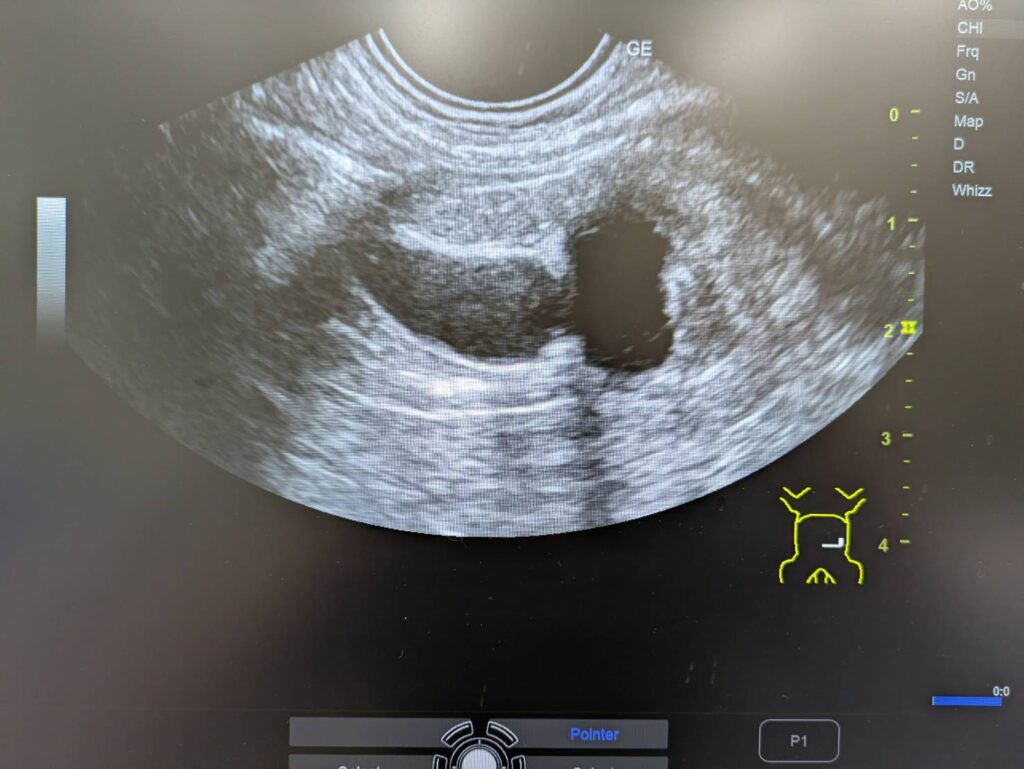

結果はこんな感じ。

左の腎臓の腎盂が重度に拡張し

その先の尿管内に結石のようなものがみつかりました。

診断は尿管閉塞による急性腎障害といった感じでしょうか。